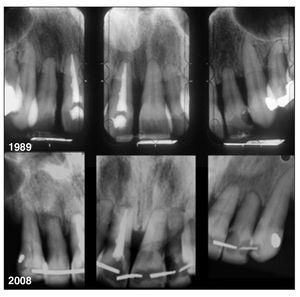

Figura 1 Radiografías periapicales realizadas en 1989 a una mujer de 31 años que muestran una amplia pérdida de hueso vertical como consecuencia de una enfermedad periodontal avanzada.

Figura 3 Estado de los dientes del maxilar superior anterior de la paciente tras 19 años. Los niveles óseos han permanecido relativamente estables. Los cuatro dientes posteriores remanentes fueron extraídos después de 15 años y sustituidos por prótesis removibles.